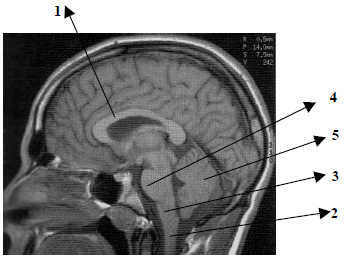

Observe atentamente o corte sagital apresentado na imagem abaixo e assinale a alternativa que apresenta a identificação correta das estruturas assinaladas.